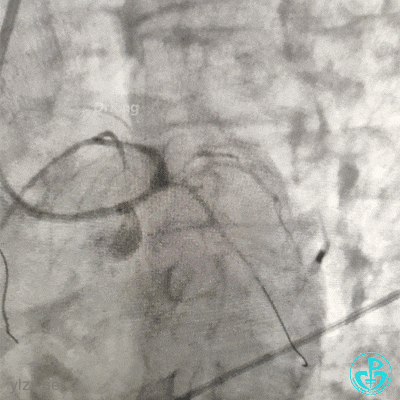

病情变化

下午18:00复查超声:

凌晨03:00复查超声:

患者于凌晨02:20左右突发心脏骤停,心电监护呈等电位线。经抢救1小时无效死亡。